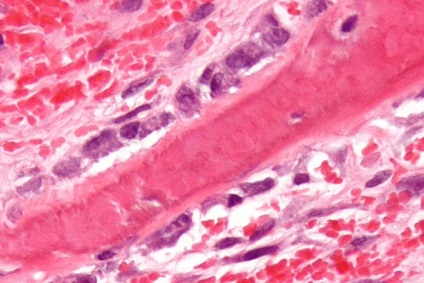

Myeloma alakul mutációja miatt érett plazmasejtek hatása alatt tényező a tumornövekedés (interleukin-6). Proplazmatsita patológiai változás hatására a tumor alkotnak egy klón, amely nem érzékeny a apoptózis és szaporodnak kontrollálatlan. Mivel egyre több rosszindulatú sejtek növekvő koncentráció és patológiás immunglobulin általuk előállított (paraproteinnel).

A kóros sejtek szaporodásának neoplasia fokozatosan felváltja a funkcionalitás. Ugyanakkor gátolja a termelés minden típusú vérsejt, amely anémiához, csökkent véralvadás és immunitás rendellenességek.

A jellemző áramlási mielomatoza feloldja a csont szakaszok helyén a patológiás sejt lokalizáció. A folyamat az élet megváltozott plazmasejtek citokineket, amelyek aktiválják az osteoclastok - különleges sejtek, amelyek részt vesznek a folyamatban csontforgalom. Amikor az egyensúly az osteoblast és osteoclast aktivitást mellett az első oldódási sebessége az ásványi komponens a csont-kollagén és megsemmisítése sokszor a képződési sebességét új szövet. Ezáltal zsebek felszívódást (megszüntetés), az érintett csontok törékennyé válnak és törékeny.

Különböző jellemzőit plazma sejtek saját módosítani, hogy osztályozni mielóma plazmotsitarnuyu, plazmoblastnuyu és gyengén differenciálódott formában. Az utóbbi esetben, a sejtek lehetnek az azonos méretű (kis mielóma) vagy különböző (polymorphocellular mielóma).